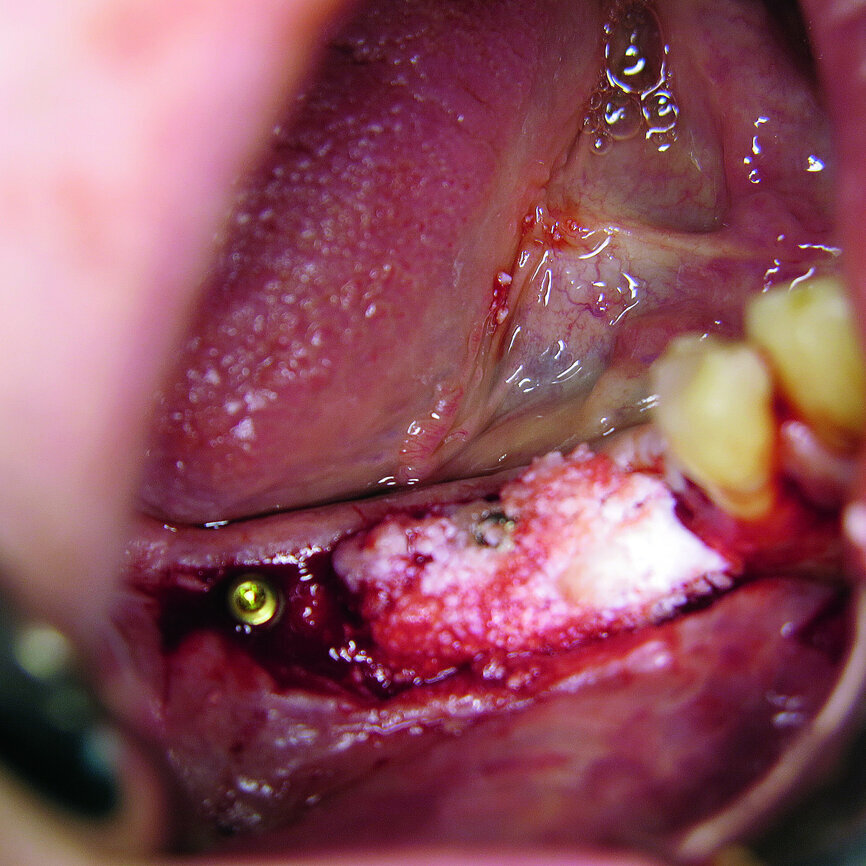

Fig. 10: 3-D augmentation using NanoBone.

In our cases NanoBone, pericard membrane (imperiOs) and autologous bone chips were used for augmentation. NanoBone is an efficient nano-structure nano-crystalline hydroxyapatite embedded in a highly porous silica gel matrix. NanoBone is a safe product and stimulates the formation of collagen and bone. As an effect, many osteoblasts are seen in the early stage of regeneration. NanoBone has been on the market three years in the form of putty. NanoBone putty has a high consistency and is optimal for use to rebuild vertical bone. In general, no additional membranes are necessary. Its special structure results in rapid bone formation. As the osteoclasts resorb the granules, NanoBone is completely substituted by bone and no foreign substances will influence natural biomechanics.

Alternatively, NanoBone block material is now on the market and is a safe and rapid solution for block augmentation. Animal studies have shown that it induces quick bone formation. It offers an alternative to autogenous bone blocks for improving the implant bed in the case of vertical and horizontal bone deficits. In two patients with defects of the lower jaw, NanoBone block was used to optimise horizontal defects. NanoBone material was fixed with CAMLOG screws and a collagen membrane was used (RESORBA Medical).